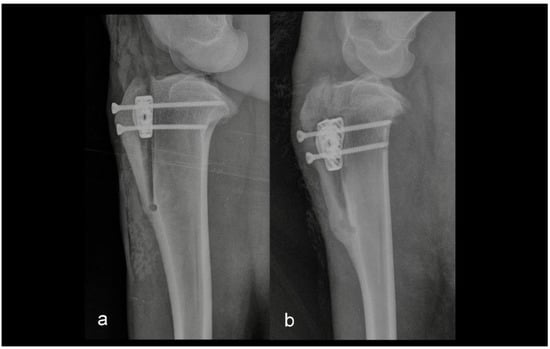

The second group consisted of five sheep in which the intraoperative or postoperative discrepancies from preoperative planning were found. Discrepancies were either the osteotomy line was too close to the tibial crest, or the tibial crest was cracked at the level of the Maquet hole (Figure 2 and Figure 3).

Figure 3. Mediolateral radiograph of the stifle in Group 2 immediately postoperatively (a) and at six months postoperatively (b). The osteotomy line was too close to the tibial tuberosity crest.